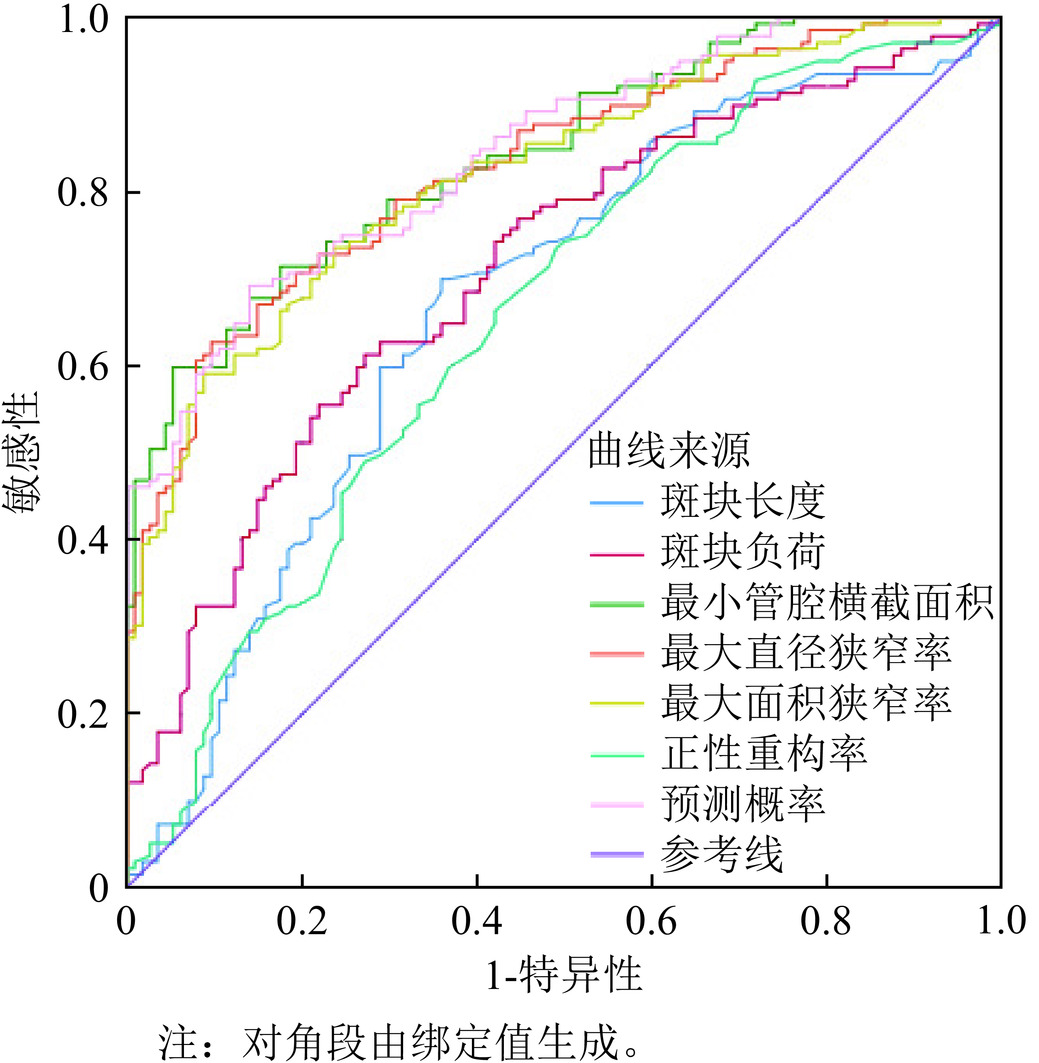

目的:比较缺血组与非缺血组的CCTA斑块特征差异,探求对诊断心肌缺血有价值的斑块特征定性及定量指标,在临床工作中应用,尽早发现可能存在心肌缺血的受检者。方法:连续纳入2022年1月至2024年12月就诊于我院心内科并接受有创冠状动脉造影测量FFR和CCTA扫描的冠心病患者进行回顾性分析。以患者水平分组分析一般资料。以血管水平分组分析CCTA斑块特征信息。斑块分析由两名具有5年以上CCTA诊断经验的放射科医师在未知分组的情况下使用半自动斑块分析软件进行。结果:研究共纳入163例患者,缺血患者组与非缺血患者组的一般资料无统计学显著差异。本研究共纳入253支血管,缺血血管组纳入114支血管,非缺血血管组纳入139支血管。斑块特征定性指标中,缺血血管组的餐巾环征、点状钙化比例高于非缺血血管组,两组的正性重构、低密度斑块指标无统计学显著差异。斑块定量指标中,两组的PL、PB、MLA、MDS、MAS、RI具有统计学显著差异,PV、EI无统计学显著差异。PL、PB、MLA、MDS、MAS、RI诊断斑块所属血管供血区域的心肌缺血的AUC分别为0.672、0.712、0.843、0.830、0.821、0.655,联合检测的AUC为0.844,高于单一指标诊断。结论:CCTA斑块特征分析在预测心肌缺血中具有很大潜力,多种斑块特征定量指标联合诊断对预测心肌缺血具有更高的效能。

Abstract:Objective: To compare the differences in coronary computed tomography angiography (CCTA) plaque characteristics between ischemic and non-ischemic groups and to explore qualitative and quantitative plaque features that are valuable for diagnosing myocardial ischemia. This study aimed to apply these indicators in clinical practice to identify patients with potential myocardial ischemia as early as possible. Methods: A retrospective analysis was conducted on patients with coronary heart disease who underwent invasive coronary angiography for fractional flow reserve (FFR) measurement and CCTA scanning in the cardiology department of our hospital between January 2022 and December 2024. General information was analyzed at the patient level, whereas CCTA plaque characteristics were analyzed at the vessel level. Plaque analysis was performed by two radiologists with more than five years of experience in CCTA diagnosis using semi-automatic plaque analysis software blinded to the patient groups. Results: A total of 163 patients were included in the study, with no statistically significant differences in general information between the ischemic and non-ischemic groups. A total of 253 vessels were included, with 114 vessels in the ischemic and 139 in the nonischemic vessel groups. Among the qualitative plaque characteristics, the napkin-ring sign and punctate calcification were more prevalent in the ischemic than in the nonischemic vessel group. No statistically significant differences were observed in positive remodeling and low-density plaque indicators between the two groups. Among the quantitative plaque characteristics, statistically significant differences in plaque length (PL), plaque burden (PB), minimum lumen area (MLA), minimum diameter stenosis (MDS), maximum area stenosis (MAS), and remodeling index (RI) were observed between the two groups. There were no statistically significant differences in plaque volume (PV) or edge irregularity (EI). The areas under the curve (AUCs) for diagnosing myocardial ischemia in the vascular supply areas of the plaques using PL, PB, MLA, MDS, MAS, and RI were 0.672, 0.712, 0.843, 0.830, 0.821, and 0.655, respectively. The AUC for the combined detection was 0.844, which was higher than that for any single indicator. Conclusion: CCTA plaque characteristic analysis has great potential for predicting myocardial ischemia, and the combined use of multiple quantitative plaque indicators provides higher diagnostic efficacy.

指标 AUC 标准误 渐进Sig 特异度(%) 灵敏度(%) 95%可信区间 PL(mm) 0.672 0.035 0.000 0.640 0.698 0.604~0.739 PB(%) 0.712 0.032 0.000 0.728 0.612 0.648~0.775 MLA(mm2) 0.843 0.024 0.000 0.863 0.676 0.796~0.889 MDS(%) 0.830 0.025 0.000 0.904 0.619 0.781~0.878 MAS(%) 0.821 0.026 0.000 0.763 0.734 0.771~0.872 RI 0.655 0.035 0.000 0.579 0.662 0.587~0.723 联合预测 0.844 0.023 0.000 0.860 0.691 0.798~0.890 表 5 斑块定量指标单一和联合预测的性能比较

指标 AUC 面积之间差异 标准误 Z统计 95%CI可信区间 P值 PL(mm) 0.672 0.172 0.034 5.085 0.106~0.239 0.000 PB(%) 0.712 0.132 0.030 4.471 0.074~0.190 0.000 MLA(mm2) 0.843 0.001 0.009 0.120 −0.016~0.019 0.904 MDS(%) 0.830 0.014 0.012 1.229 −0.008~0.037 0.220 MAS(%) 0.821 0.022 0.015 1.503 −0.007~0.052 0.133 RI 0.655 0.188 0.037 5.152 0.117~0.260 0.000 联合预测 0.844 -